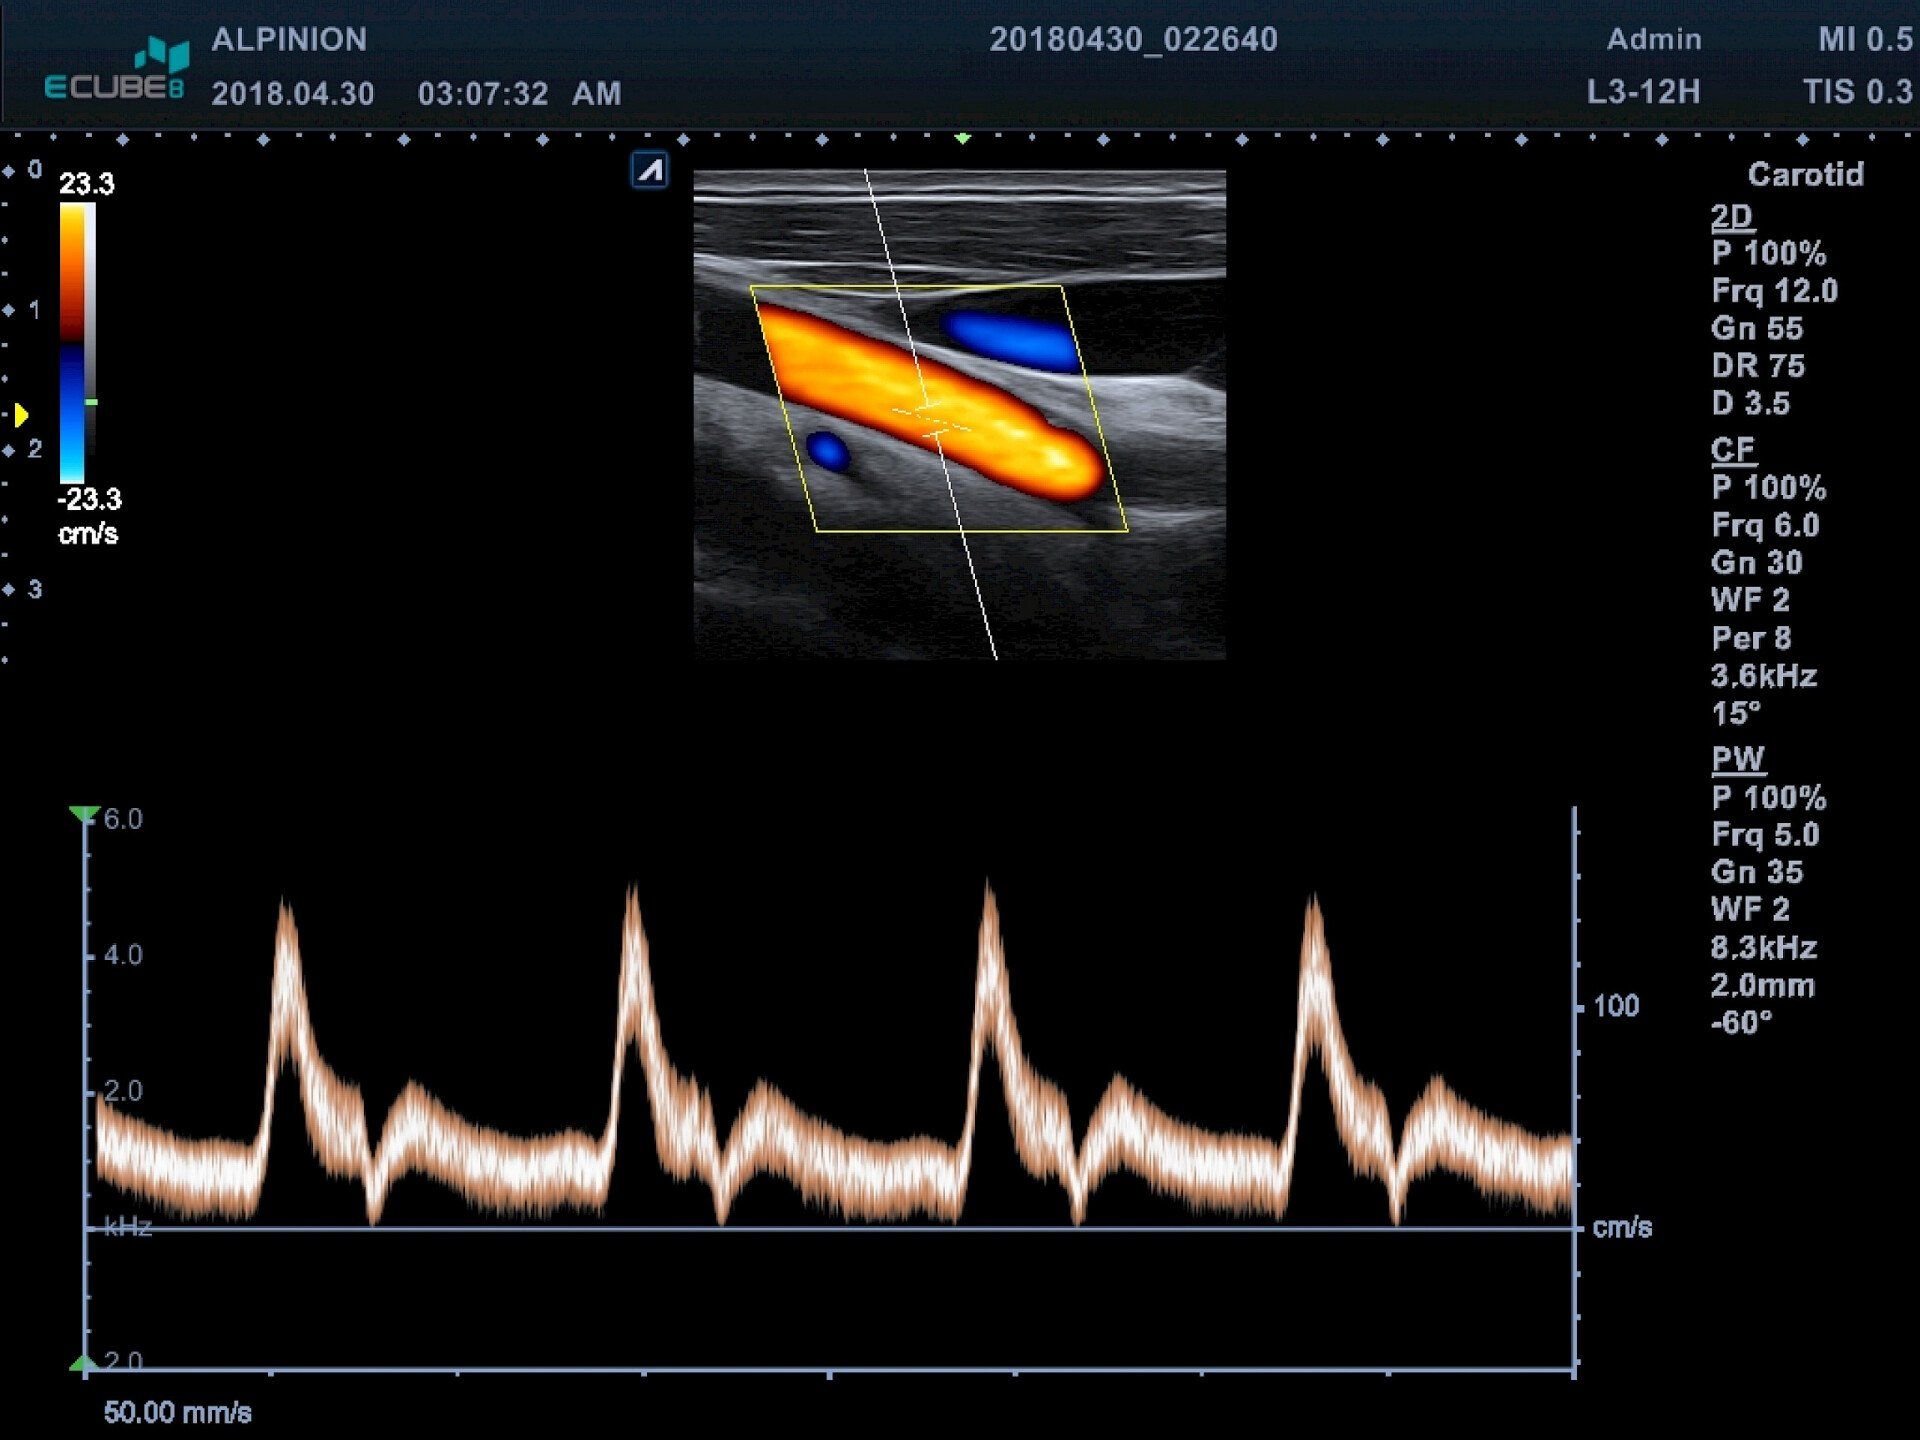

Mit Ultraschall wird hierbei die Dicke der innersten Schicht der Blutgefäße (Intima-Media-Dicke = IMT) gemessen.

Man kann aus dieser Messung Rückschlüße über beginnende Gefäßverkalkung (Arteriosklerose) ziehen. Frühe Stadien dieser Erkrankung lassen sich so hervorragend messen.